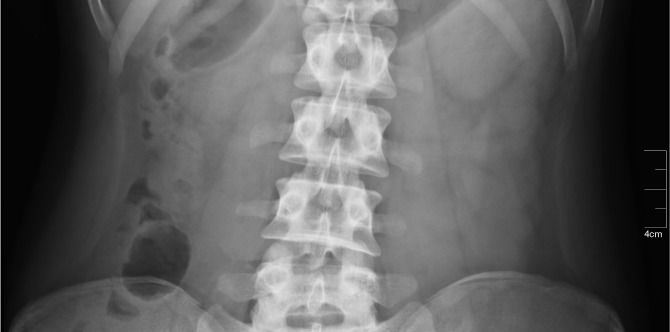

What Is Crohns Disease And How Can It Affect My Family?

Image source: iStock